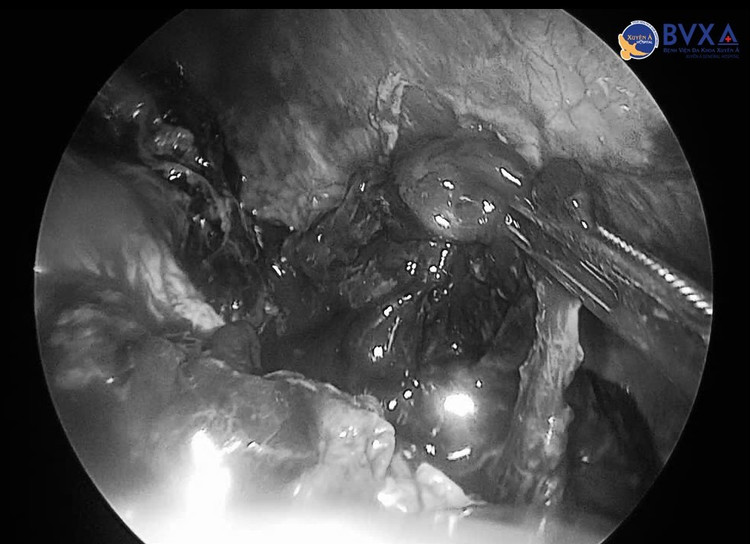

tran-mau-3.jpg

Nội soi phổi cho bệnh nhân - Ảnh BVCC

Trong vòng 2 giờ, các bác sĩ đã tiến hành dẫn lưu màng phổi phải, đồng thời nội soi lồng ngực lấy máu đông màng phổi trái. Với kỹ thuật gây mê thông khí một phổi, ê-kíp vừa xử lý các điểm chảy máu, vừa làm sạch khoang màng phổi hai bên một cách chính xác và an toàn.